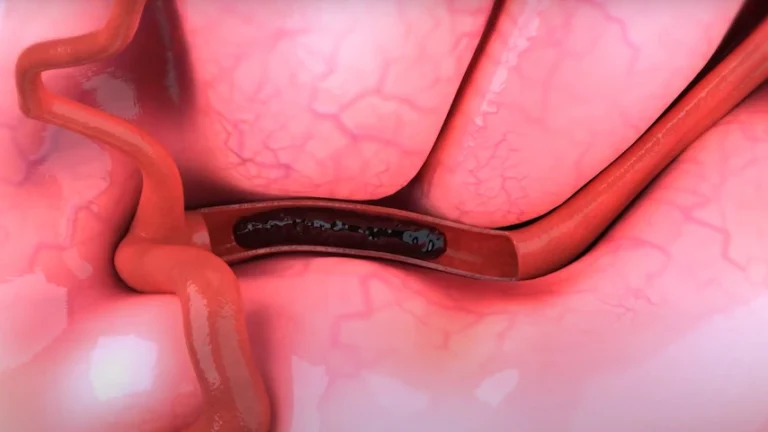

فناوری نوین «عصبزدایی لگنچه کلیه»؛ رویکردی جدید برای درمان هدفمند فشار خون بالا شرکت وِرو مِدیکال (Verve Medical) با معرفی فناوری نوآورانه «عصبزدایی لگنچه کلیه» (Renal Pelvic Denervation یا RPD)، گام تازهای در درمان بیماران مبتلا به فشار خون کنترلنشده برداشته است؛ رویکردی که میتواند رقابت جدیدی را در بازار درمانهای مداخلهای فشار خون…